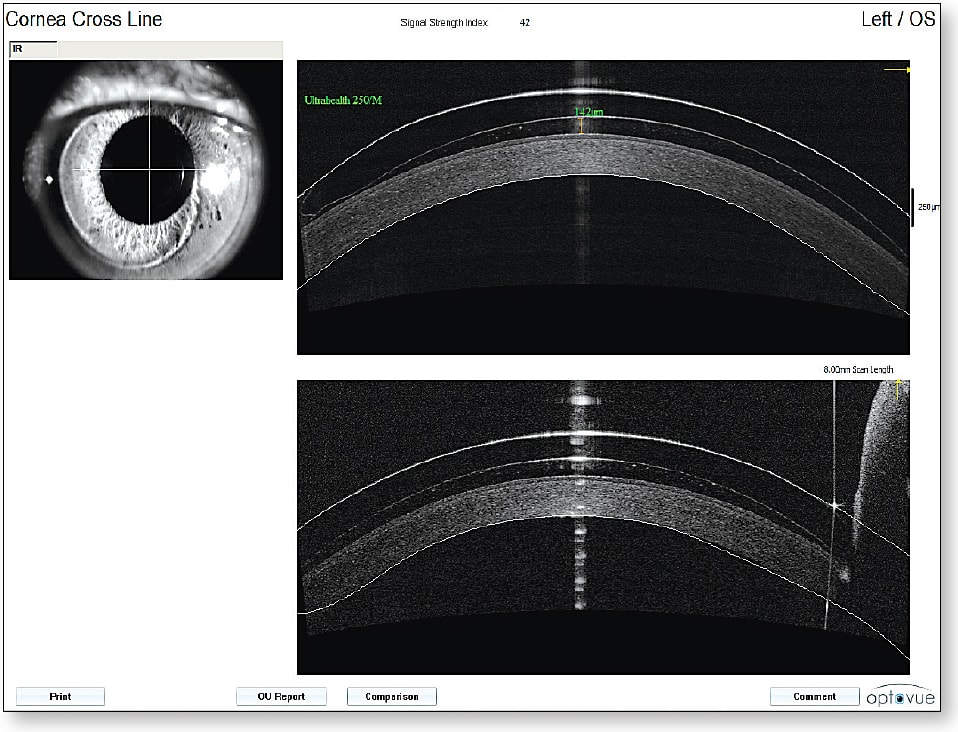

Anterior Segment Optical Coherence Tomography (AS-OCT) AS-OCT provides exquisite images of the cornea and other structures of the anterior segment of the eye. Not only can we obtain these images for viewing, but we can use various tools provided within the systems to measure various elements of anterior segment structures, such as corneal diameter, corneal sagittal height, corneo-scleral sagittal height, anterior chamber angles, anterior chamber depth, and many more (Figure 8). Developing software programs are now allowing us to measure not only global corneal thickness, but also epithelial and stromal thickness. Normative database analysis will soon enable us to identify patients who are, for example, suspects for early keratoconus.

There has been a dramatic expansion in the use of AS-OCT to evaluate the fitting characteristics of vaulting contact lenses such as scleral lenses and vaulting hybrid lenses. Precise measurements of the retro-lens tear layer and the landing areas of these lenses allow practitioners to far more precisely establish optimal fitting relationships (Figure 9). We have come to further understand that the vaulting and landing appearance at initial dispensing of these contact lenses can significantly change following hours of settling on the eye. AS-OCT allows us to quantify this settling phenomenon. In fact, new software programs for AS-OCT are allowing the systems to automate the vaulting measurements without having to manually measure various areas of lens vault (Figure 10). In essence, AS-OCT is revolutionizing the assessment of vaulting contact lenses, and the technology is being developed that will allow for virtual fitting of such lenses from AS-OCT measurements.